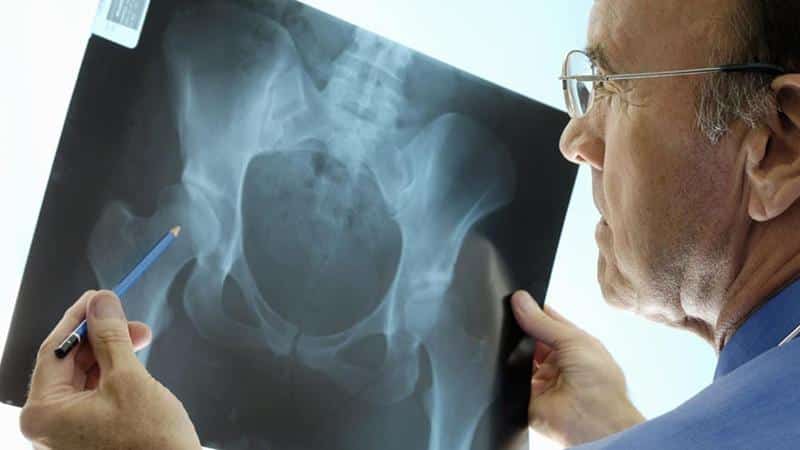

На рентгеновском снимке хорошо видно кости

- Рентген. Благодаря своей специфике рентгенография может стать прекрасной заменой МРТ.